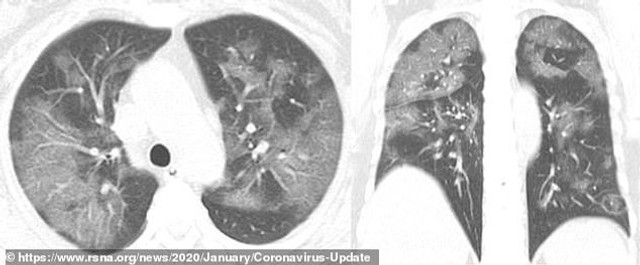

Skener 41 Godisnje Zene Najbolje Pokazuje Na Koji Nacin Korona Virus Unistava Nasa Pluca Telegraf Rs

Zobacz Jak Koronawirus Niszczy Pluca Naukowcy Z Akademii Medycznej W Czengdu Udostepniaja Zdjecia Wp Abczdrowie